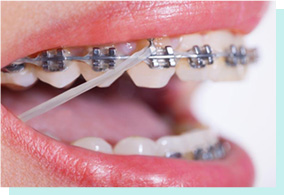

複診間隔較傳統矯正延長至少4周

托槽邊緣更圓潤,降低黏膜刺激

美化弓絲與托槽,遠距離更隱形